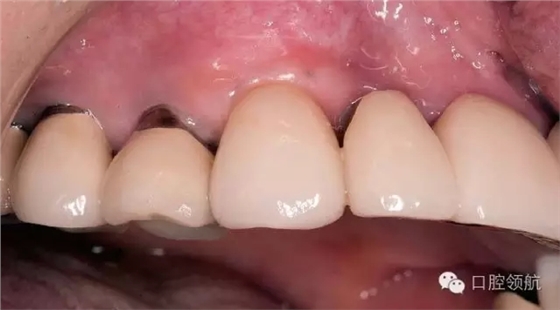

(左上第4顆牙)種植體周圍骨組織吸收的原因是種植體植入的位點(diǎn)偏頰側(cè),植入的方向也向頰側(cè)傾斜,考慮到以上原因,按照正確的種植體位置和方向植入后(圖3),上部修復(fù)體是使用氧化鈷為基底的全瓷冠,采用螺絲直接固位到種植體上的構(gòu)造(圖4~圖6)。

圖3 (左上第3顆牙) 的種植體在修復(fù)前的口腔內(nèi)形態(tài),為了唇頰側(cè)有充足的骨板支持,選用了直徑稍細(xì)的種植體植入骨組織內(nèi)。

圖4 為了避免遠(yuǎn)期種植體周圍軟組織的萎縮,防止種植體頸部的金屬暴露,制作了氧化鈷為基底的全瓷冠,然后直接固定在種植體上的連接構(gòu)造上。

圖5 在(左上第3顆牙) 的種植體上,用螺絲固定的方式固定氧化鈷的全瓷冠,(左上第4、5顆牙) 部位種植體頸部的金屬暴露。計(jì)劃今后再進(jìn)行處理。